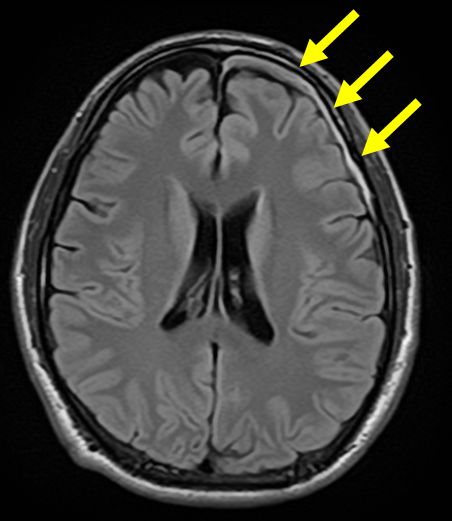

慢性硬膜下血腫の典型的な画像

頭痛を主訴とした若い患者さんの慢性硬膜下血腫の例

高齢者と異なり、頭痛が主要な症状として現れることがあります。この画像では、頭蓋骨の内側に少量の血腫が確認できます。

一カ月前に転倒し頭部打撲。転倒当日CT検査を行い異常なし。転倒から一カ月後から返答がうわのそら、さらに歩行時のふらつきが目立つようになり受診

→に血腫を認める。血腫による圧迫により健常側に見られる脳のしわ(→)が潰れている。

→に厚い血腫を認める